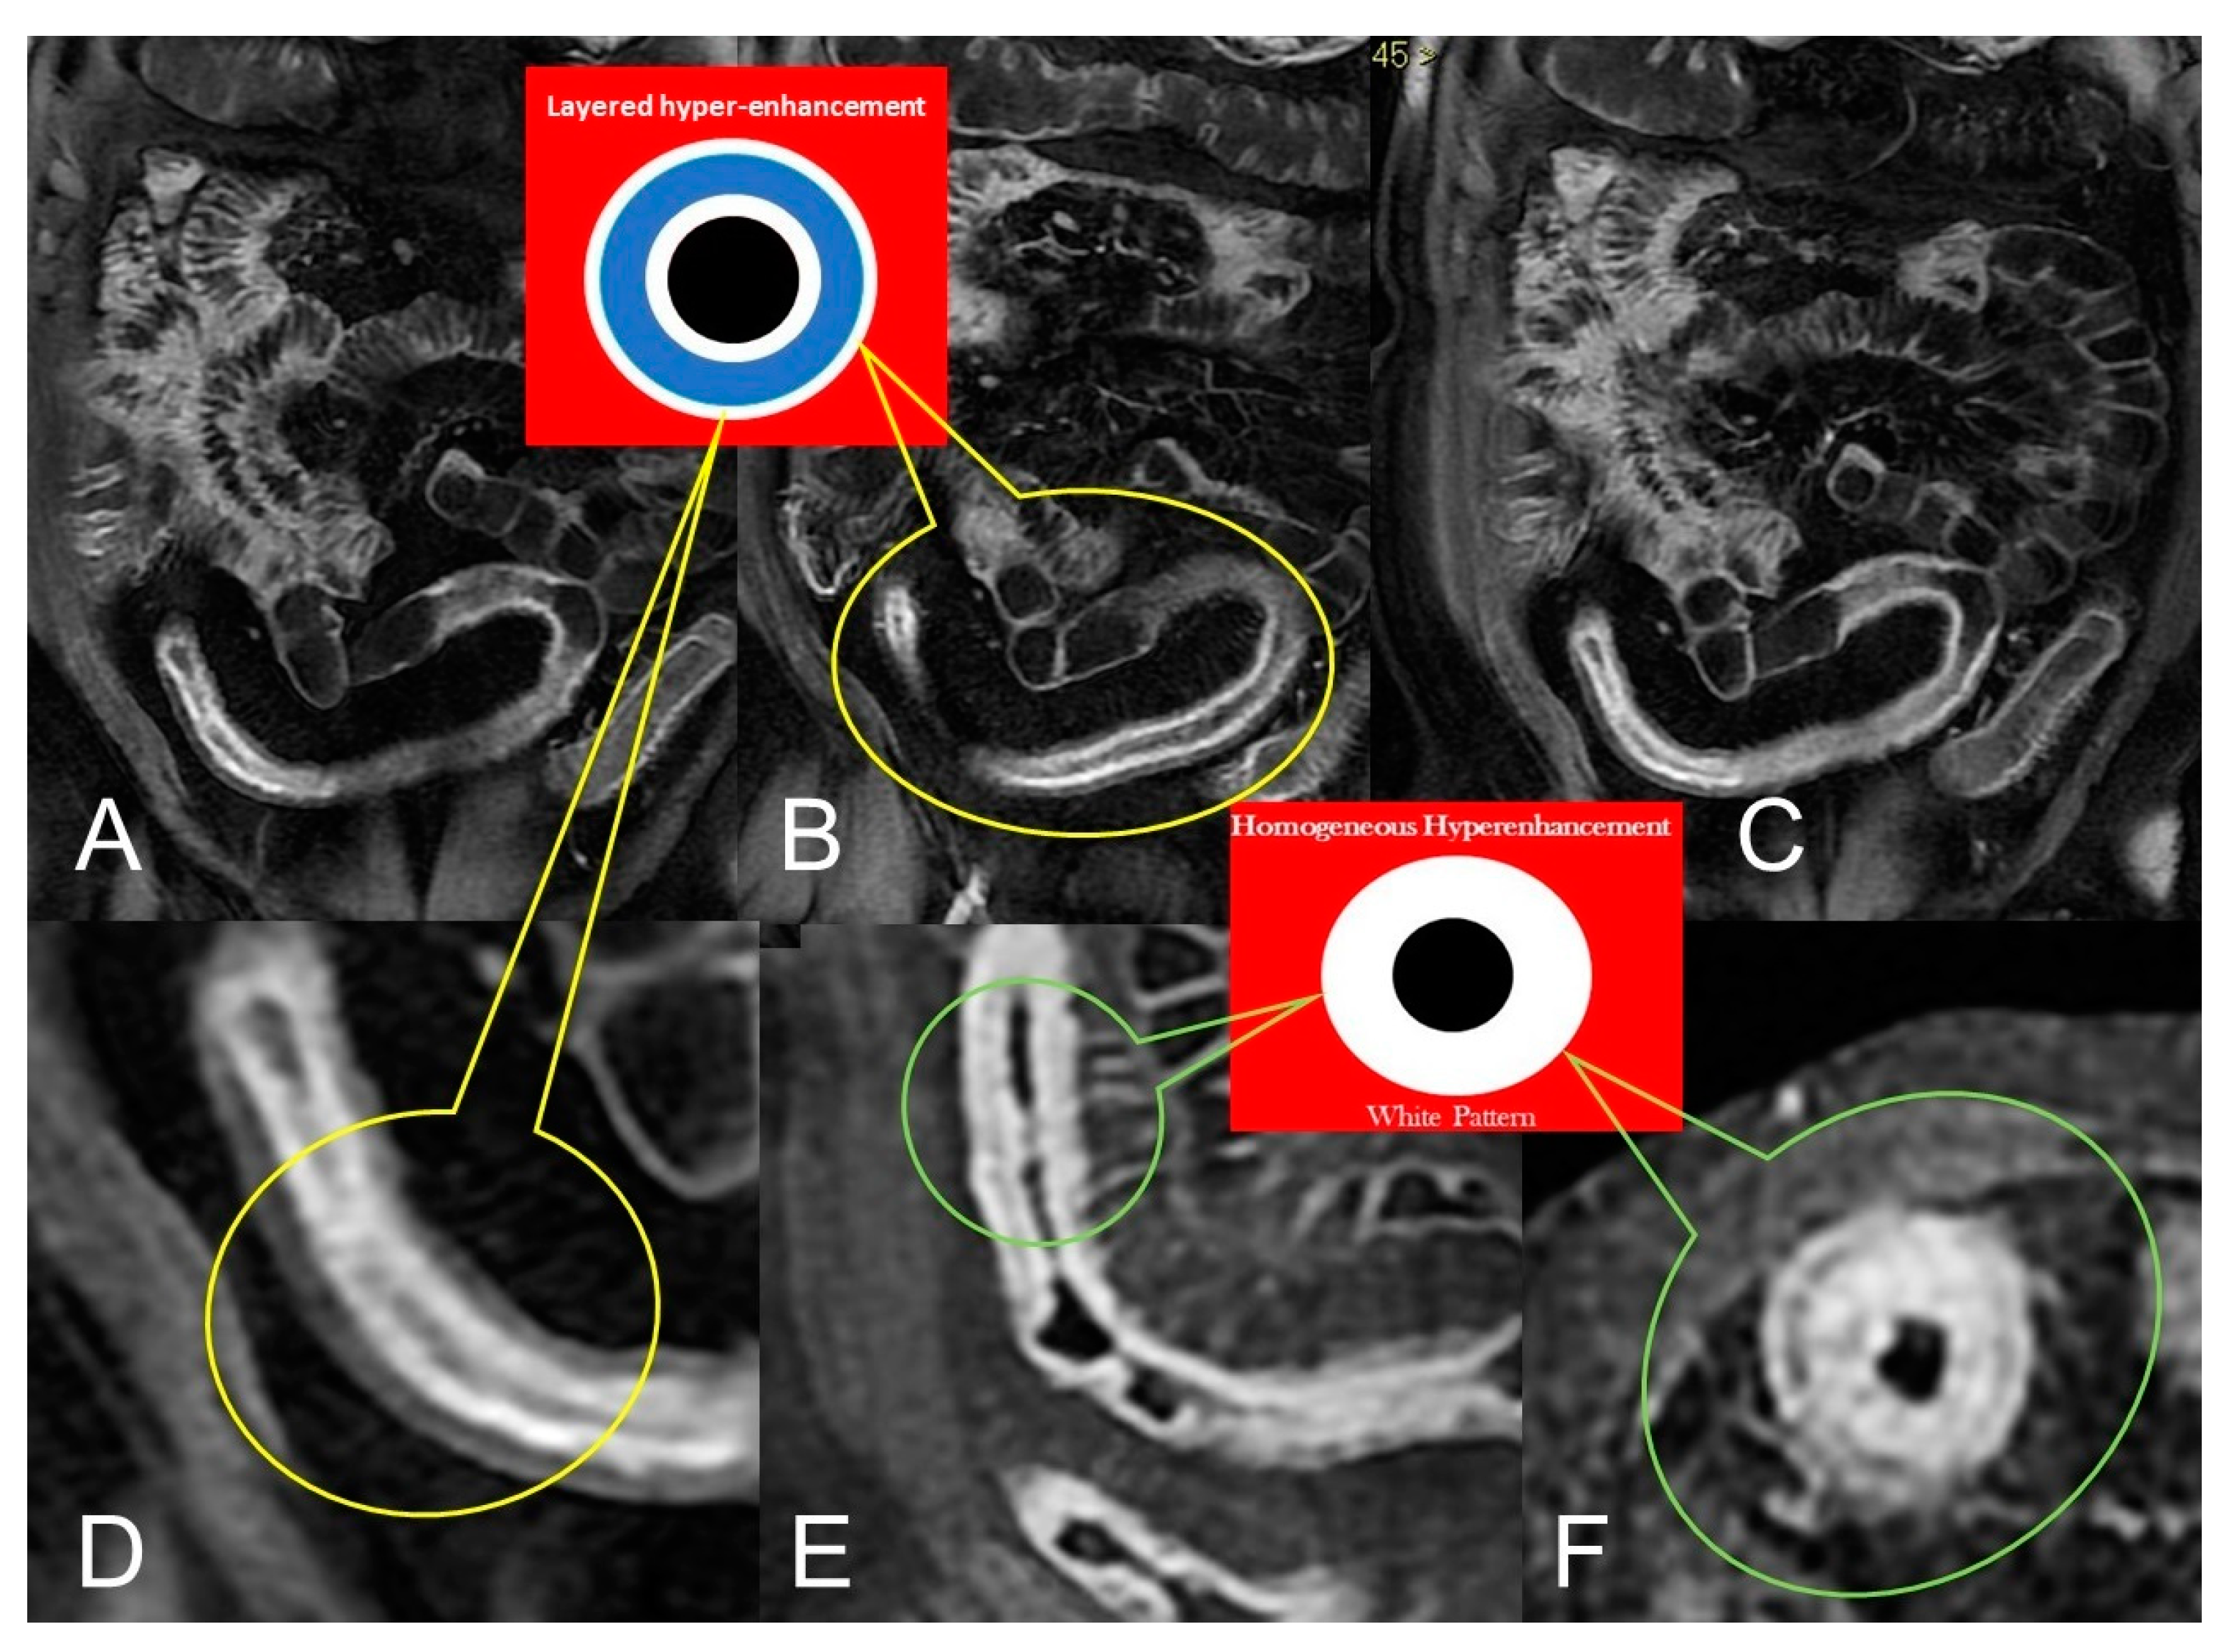

In CD, segmental bowel wall mural hyperenhancement represents the pathological tissue that at contrast-enhanced MRE is revealed as increased mural signal intensity in a small bowel’s segment compared with the normal adjacent intestinal tract [5]. Mural hyperenhancement can be asymmetric (in a small bowel loop, it could involve the mesenteric border more than the antimesenteric one), stratified (bilaminar or trilaminar inner-wall hyperenhancement or halo sign), or homogeneous (evenly distributed over the entire bowel wall). Submucosal edema, granulation tissue, intramural fat accumulation, fibrosis, or inflammatory infiltration may contribute to stratified enhancement (Figure 3 and Figure 4). Bowel wall enhancement evaluation is correctly depicted in the enteric phase (45–50 s after the intravenous contrast material injection begins) and/or in portal venous phase (60–70 s after the intravenous contrast material injection begins). Furthermore, we consider also that endoscopy and histopathological examination clearly show the absence of mucosa in the affected intestinal segments, so the term “mucosal hyperenhancement” is incorrect when the stratified enhancement pattern is expressed and should not be used. Finally, it must be underlined that the segmental bowel wall mural hyperenhancement is a sensitive but non-specific sign of CD, and therefore it must always be contextualized in the general framework of interpretation [6].

Figure 3.

Active inflammatory Crohn’s disease with layered hyper-enhancement pattern (A–D): the presence of active Crohn’s disease is indicated by small bowel wall thickening with layered hyperenhancement on coronal fat-suppressed contrast-Enhanced T1-Weighted MRE images. Active inflammatory Crohn’s disease with homogeneous enhancement pattern (E,F): the presence of active Crohn’s disease is indicated by small bowel wall thickening with homogeneous enhancement on coronal (E) and axial (F) fat-suppressed contrast-Enhanced T1-Weighted MRE images.